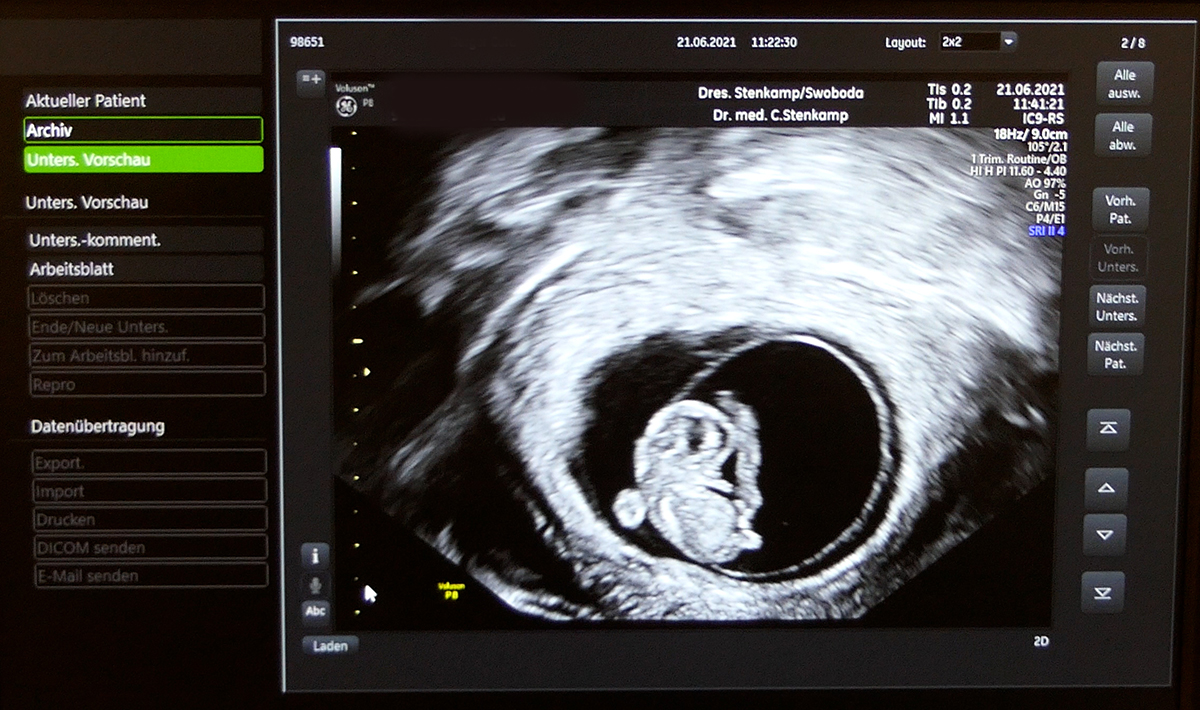

Anspruch auf gesetzlich geregelten Ultraschall

Gesetzlich hat jede Schwangere Anspruch auf drei Ultraschall -

Darüber hinaus bieten wir im Rahmen von IGEL (individuelle Gesundheitsleistungen auf privater Basis) noch folgende Unterschungen an:

Ultraschall -

Schwangerschaftsultraschall für den werdenden Papa

Untersuchung außerhalb der regulären Vorsorgetermine;

auch am Wochenende

Bei allen Ultraschall -